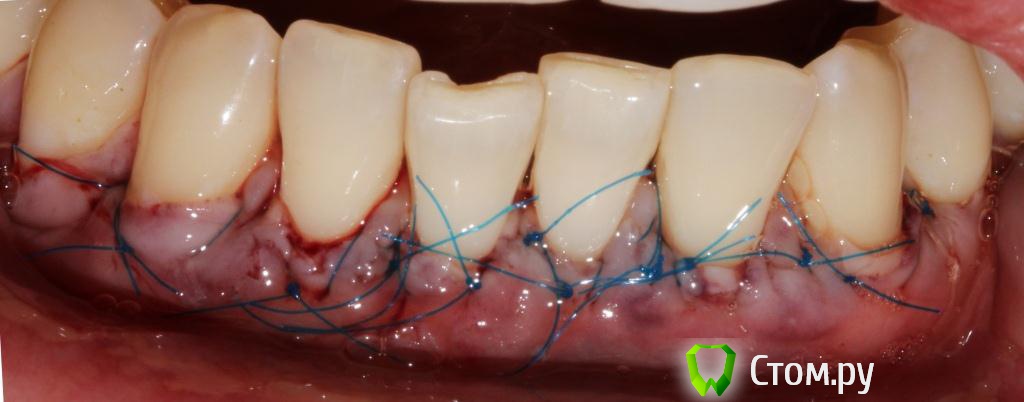

Популярный пост zzkz Опубликовано 18 сентября, 2014 Популярный пост Поделиться Опубликовано 18 сентября, 2014 (изменено) Жалобы эстетические и сильная чувствительность Рецессия от 34 до 44 Подготовка поверхности корней только скэйлинг СДТ с 2-х сторонНа небе каппа Ушивание пролен 6-0 2 недели после Чувствительности нет на сегондя. Ждать ли еще убыли или прироста? Сосочек закрыл "черный треугольник". Не уйдет ли? Изменено 18 сентября, 2014 пользователем zzkz 33 Ссылка на комментарий

Acidrocker Опубликовано 18 сентября, 2014 Поделиться Опубликовано 18 сентября, 2014 отлично) швы обвивные?) Ссылка на комментарий

zzkz Опубликовано 18 сентября, 2014 Автор Поделиться Опубликовано 18 сентября, 2014 отлично) швы обвивные?)да вроде обвивные) если честно как они правильно называются не знаю 1 Ссылка на комментарий